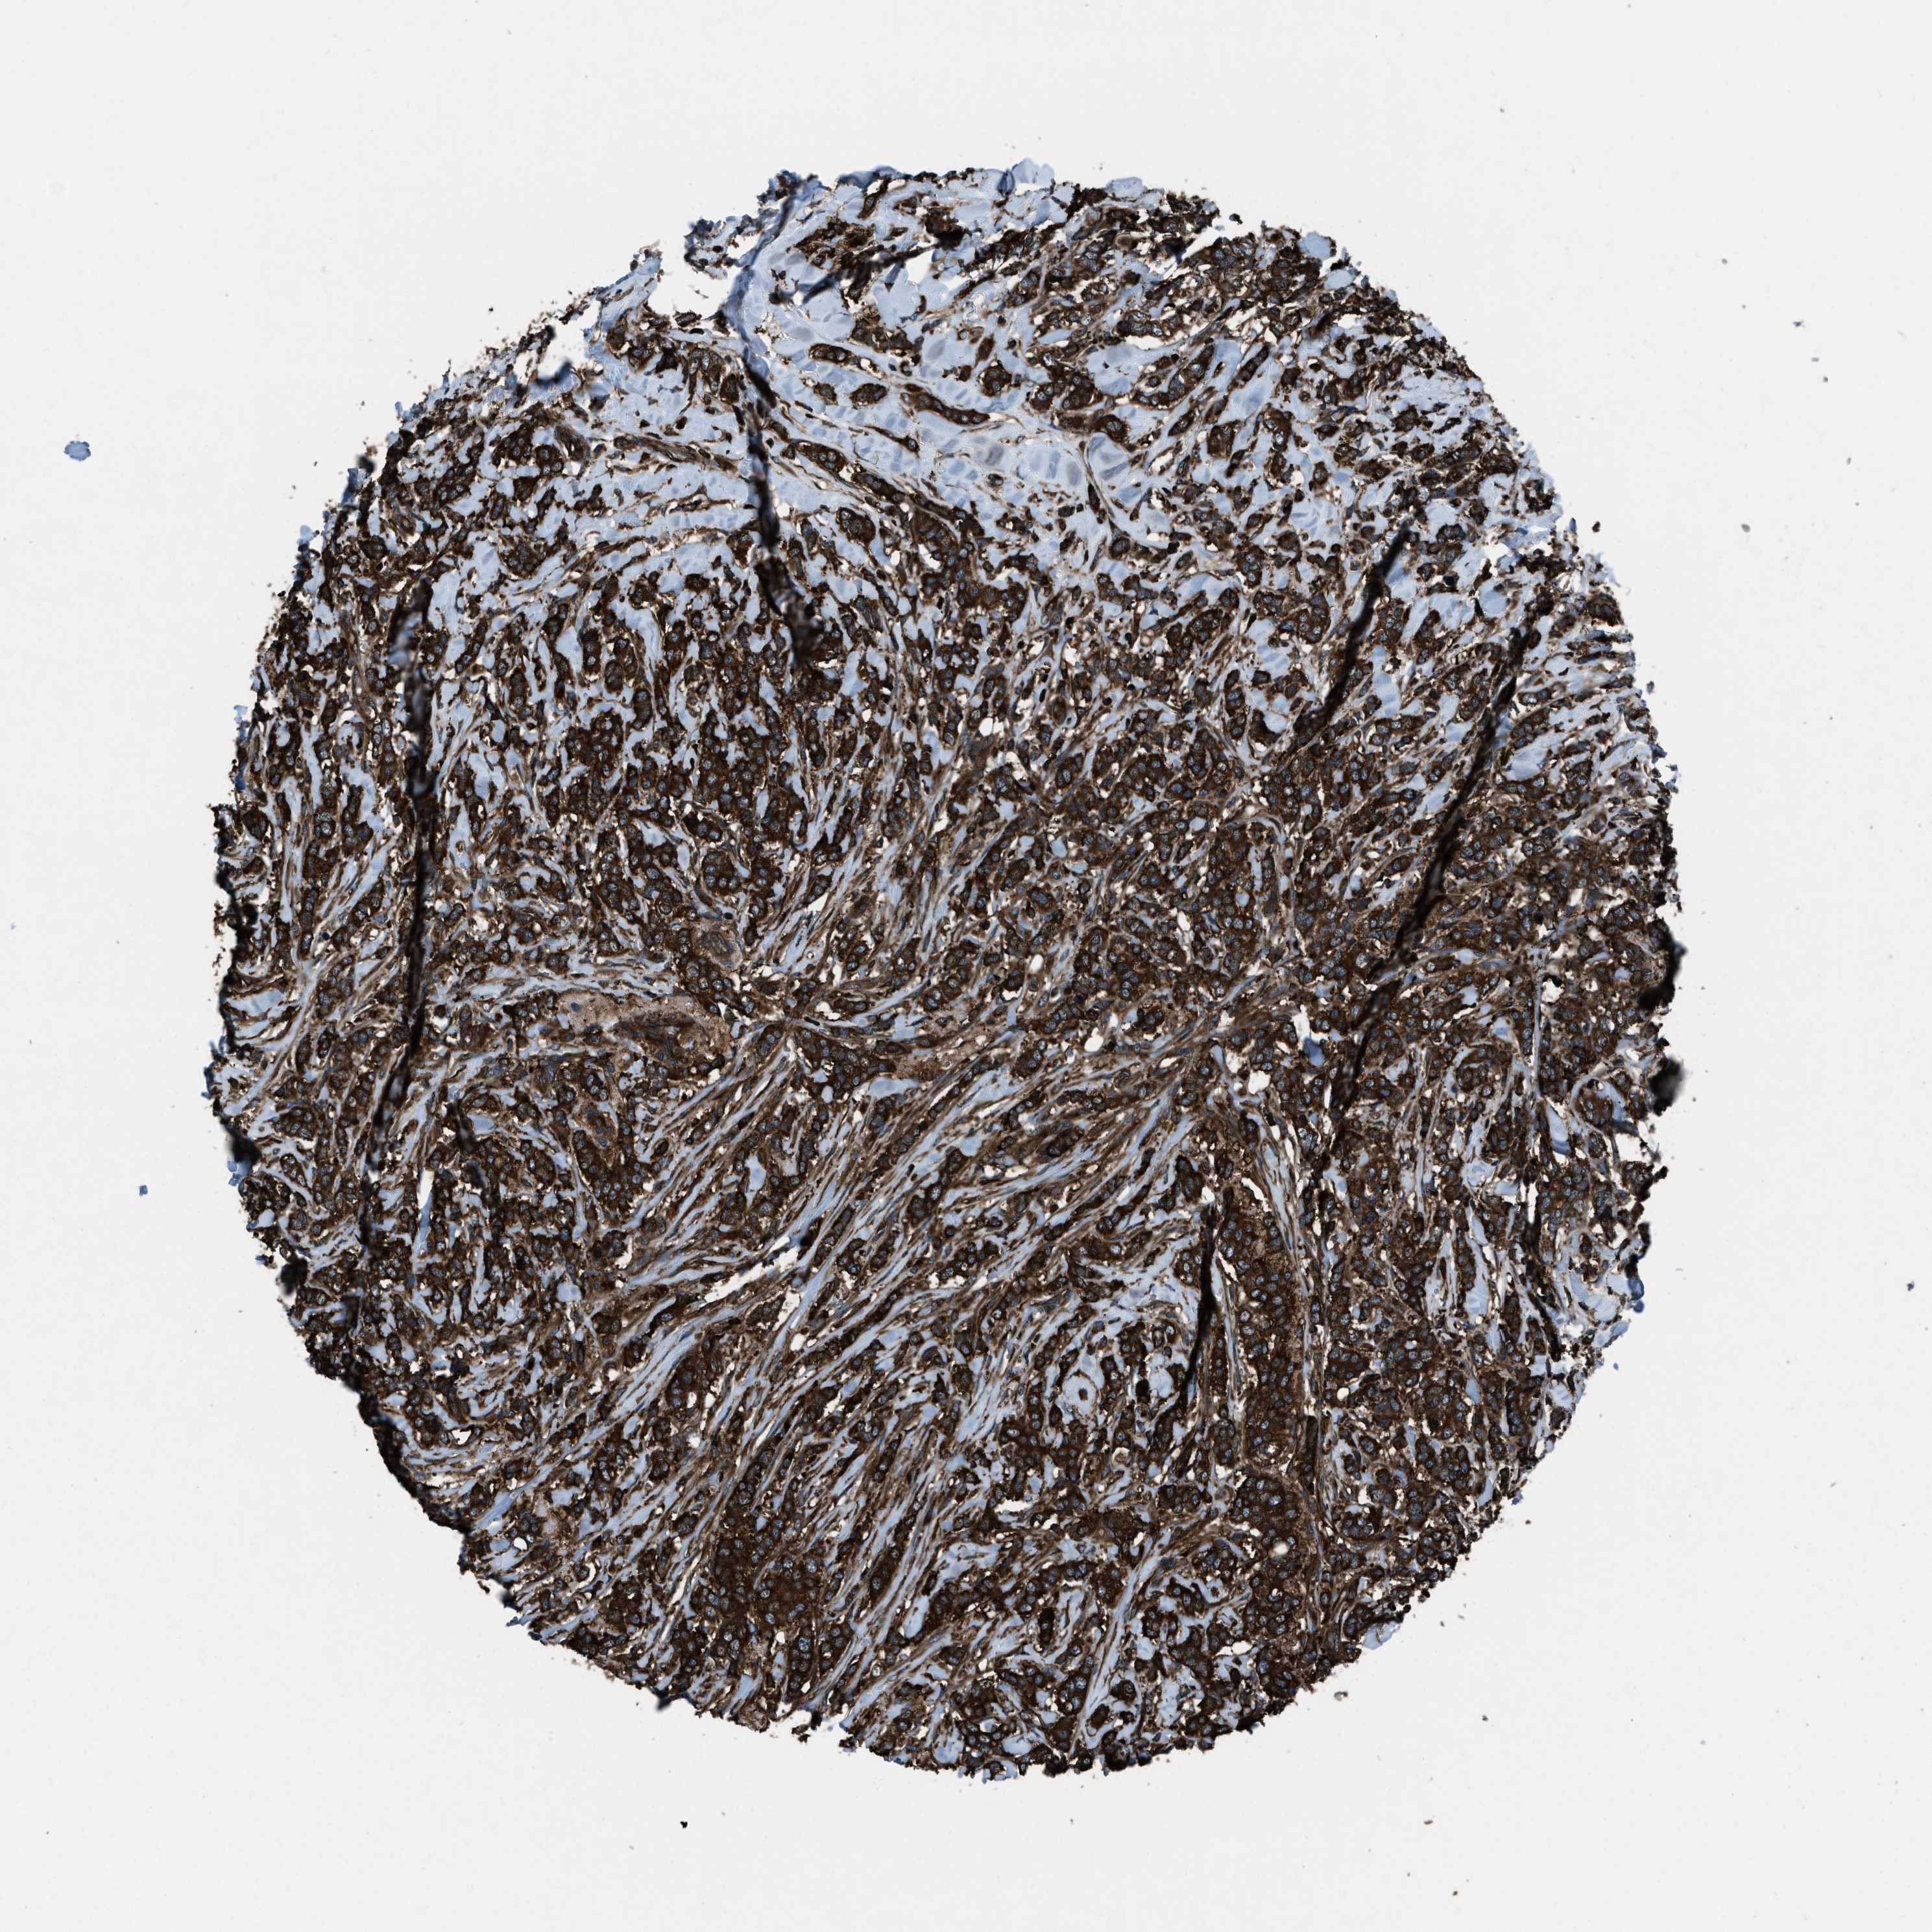

CANCER BREAST CANCER Show tissue menu

BRCA TCGA BRCA VALIDATION PROTEIN EXPRESSION